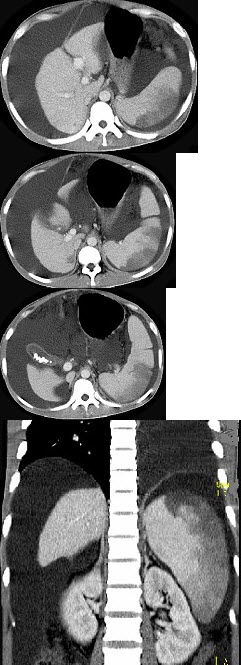

患者男,29岁,乙肝病史10余年,腹胀,有移动性浊音,影像检查如图,最全面的诊断是( )

A:肝硬化

B:肝硬化腹水

C:肝硬化腹水、脾梗、胆囊结石

D:大网膜膈下间位及脾梗

E:胆结石及脾梗